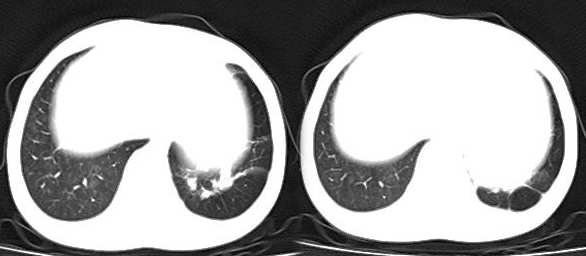

以下是引用x线在2006-2-2 17:37:00的发言:[br]结合病史支持“ct拟诊:双侧tb,左下叶结核球,左下叶局限性轻度支扩。”双下叶及左舌叶淡薄的毛玻璃密度影,我考虑为炎性渗出。另:是否合并霉菌感染须进一步检查确定。